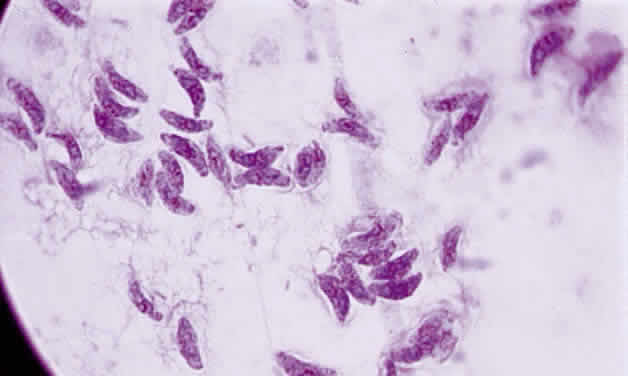

Tachyzoite is the proliferative form of the organism, which used to be known as trophozoite. It has a crescent shape and measures approximately 7 μm in length and 3 μm in width (Fig. 1). The organism is motile with a unique cytoskeletal structure allowing it to twist, wiggle, rotate, and glide. The rostrum of the tachyzoite is known as the conoid, which can extend, retract, tilt, and rotate. These movements allow the tachyzoite to find its target host cell and to penetrate the cell, establishing an intracellular existence. Tachyzoites are easily propagated in peritoneal cavities of mice and in mammalian tissue culture cell lines. The organism has the ability to replicate in all mammalian nucleated cells. In the host cell, the tachyzoite multiplies by endodyogeny; this reproductive process is susceptible to heat, freezing and thawing, desiccation, and gastric enzymes.